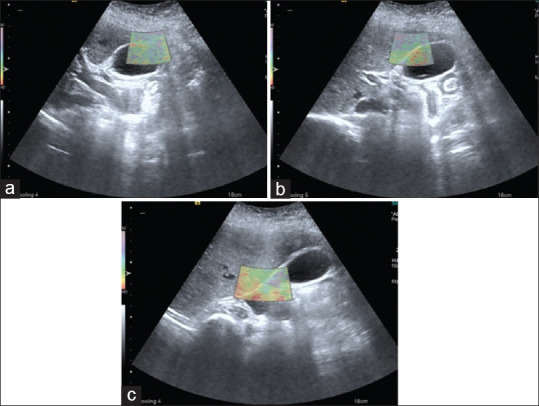

|   图 1

胆囊在三个部位的 VTI 图像(a)胆囊底、(b)胆体和(c)胆囊颈部,胆囊颈部有 E1 级粘连。VTI:虚拟触摸成像